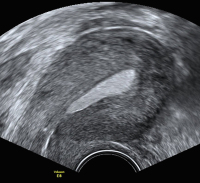

Ultraschall-Serometra

Abbildung 2: Serometra unter IVF-Stimulation: Nach Fehldosierung bildete sich eine Ansammlung eher echodenser Flüssigkeit im Cavum uteri, sodass der Zyklus abgebrochen werden musste.

Keywords: Cavum uteriGynäkologieIVF-StimulationSerometraSonographieUltraschall